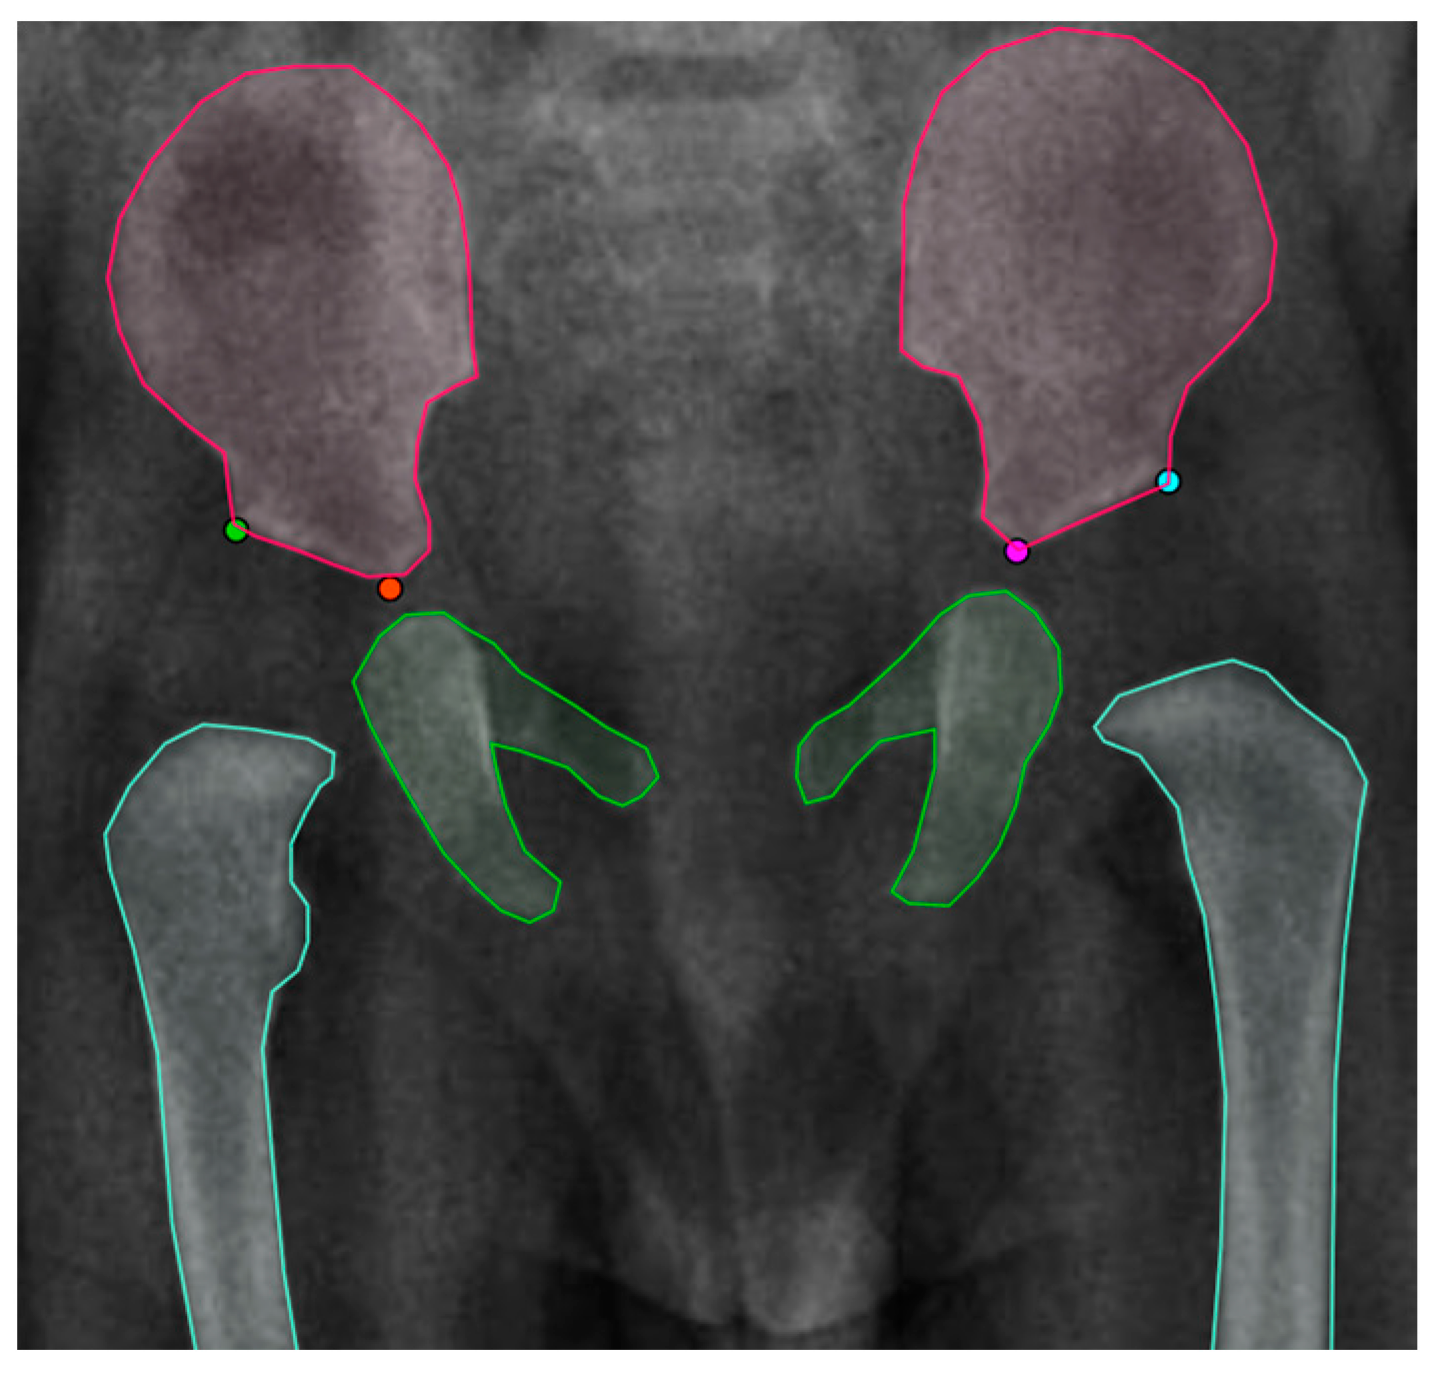

2.1. Data Annotation

3.2.1. First Stage: Instance Segmentation

3.2.2. Second Stage: Landmark Detection